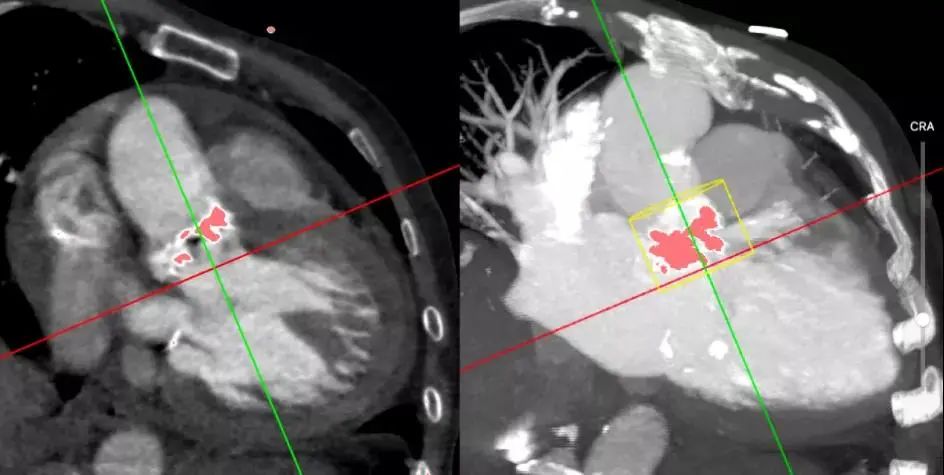

主动脉CT

瓣环:90.6mm

左室流出道:85.6mm

STJ 104.5mm

STJ距离瓣环26.6mm

升主 124.9mm Sinus 125.9mm D1:40.1mm D2:36.6mm D3:36.8mm

钙化形态及分布

钙化积分Hu850:2050

瓣膜解剖:三叶瓣,瓣环90.9mm,LOVT 95.6m,重度钙化,钙化主要分布在瓣叶边缘,瓣叶增厚,左冠高度13.7mm,存在一定的冠脉风险,主动脉瓣窦部及升部增宽,左房左室增大左室壁增厚;过弓轻柔。

瓣膜选择:使用 30mm VitaFlow瓣膜(高裙边瓣膜)。